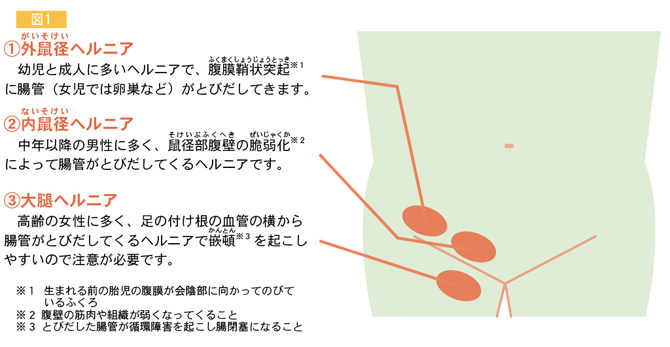

鼠径ヘルニア 脱腸 について 子どもだけじゃない 成人も要注意 かりゆし会の広報誌 あすなろ